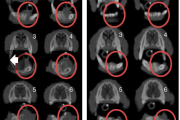

B vitamiini puudus